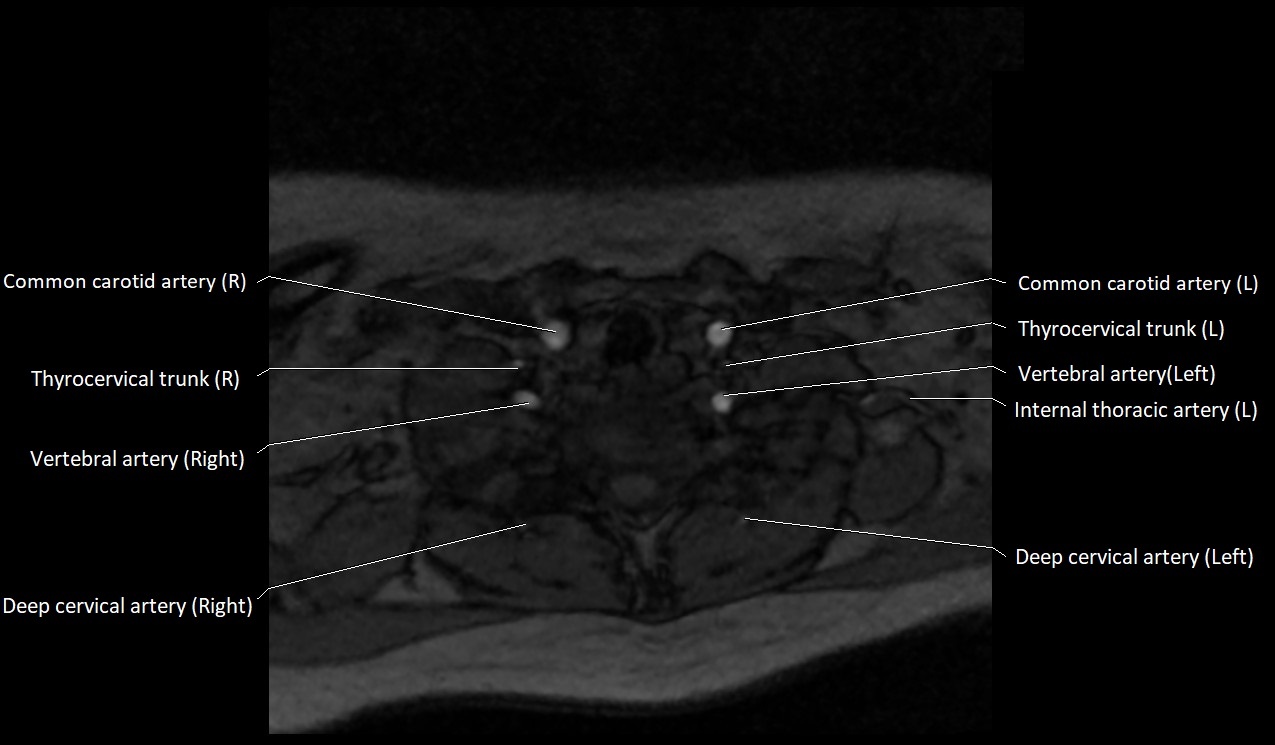

CT image

image